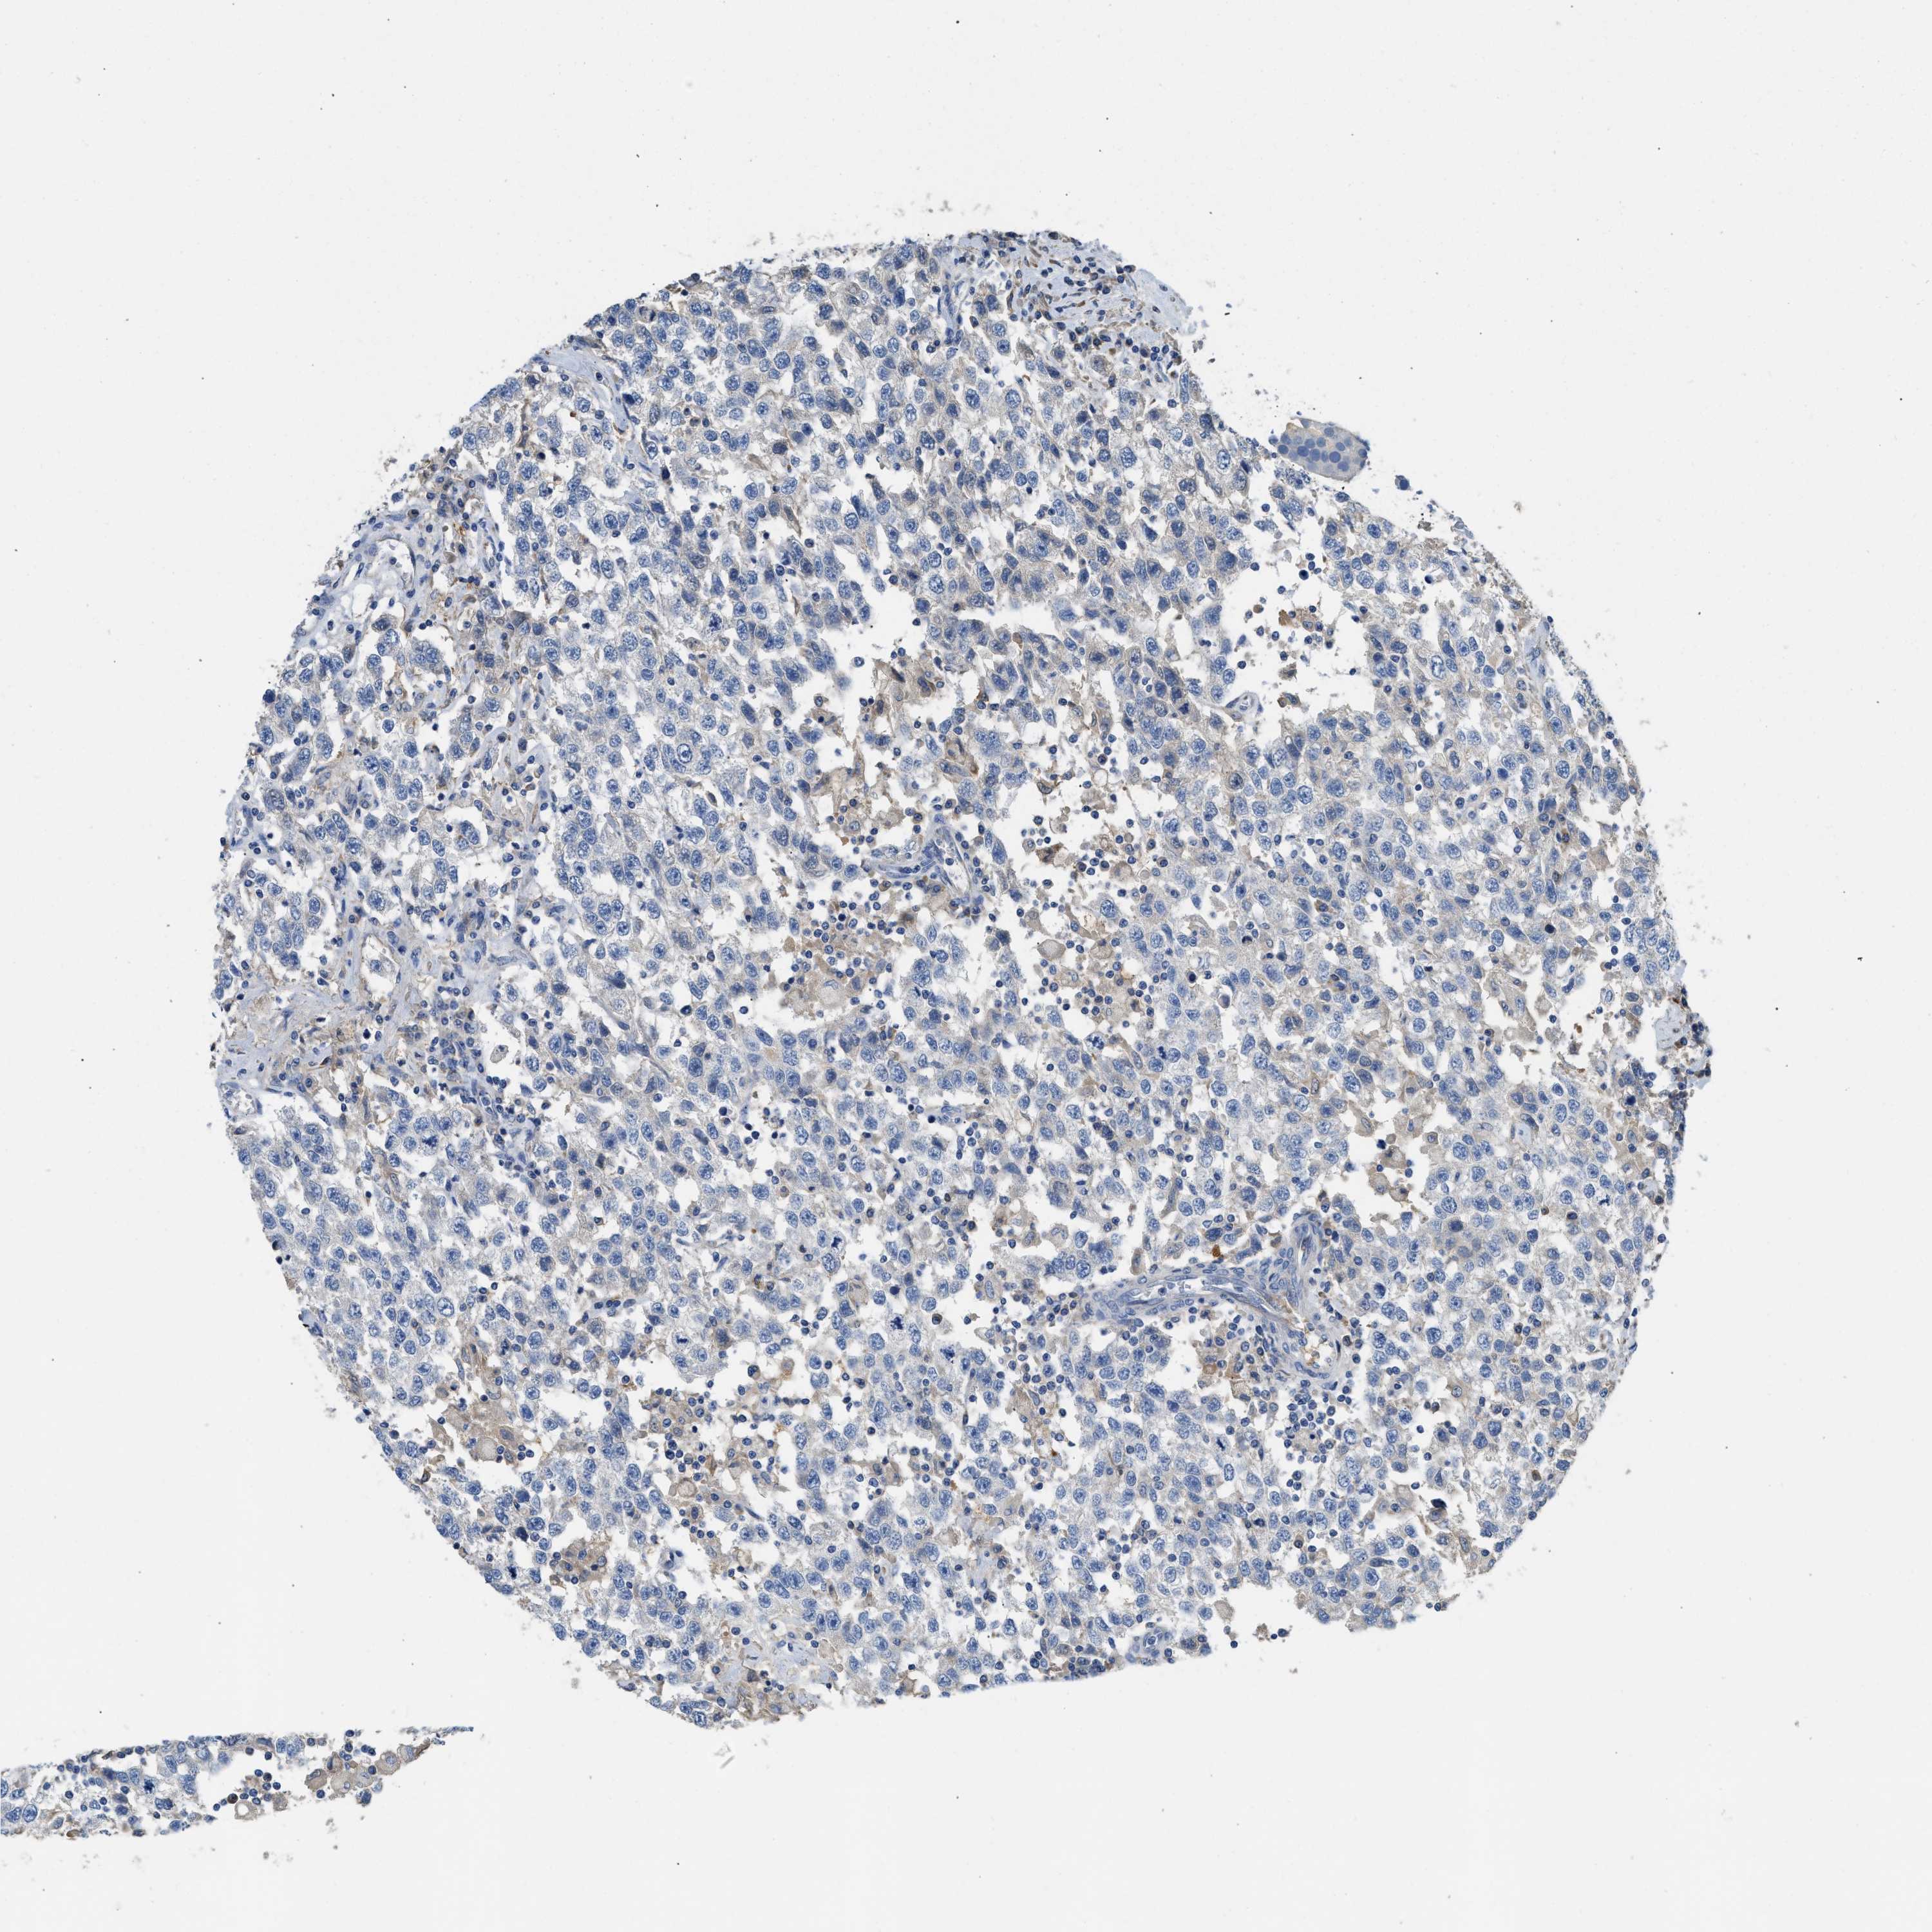

TESTIS CANCER - Protein expressioni

A mouse-over function shows sample information and annotation data. Click on an image to view it in a full screen mode. Samples can be filtered based on level of antibody staining by selecting one or several of the following categories: high, medium, low and not detected. The assay and annotation is described here.

Note that samples used for immunohistochemistry by the Human Protein Atlas do not correspond to samples in the TCGA dataset.

Antibody stainingi

Antibody staining in the annotated cell types in the current human tissue is reported as not detected, low, medium, or high, based on conventional immunohistochemistry profiling in selected tissues. This score is based on the combination of the staining intensity and fraction of stained cells.

Each image is clickable and will lead to virtual microscopy that enables deeper exploration of all samples and also displays staining intensity scores, fraction scores and subcellular localization as well as patient and tissue information for each sample.

Antibody HPA018852

Antibody CAB016722

Staining

High

Medium

Low

Not detected

Intensity

Strong

Moderate

Weak

Negative

Quantity

>75%

75%-25%

<25%

None

Location

Nuclear

Cytoplasmic/membranous

Cytoplasmic/membranous,nuclear

Carcinoma, Embryonal, NOS

Seminoma, NOS